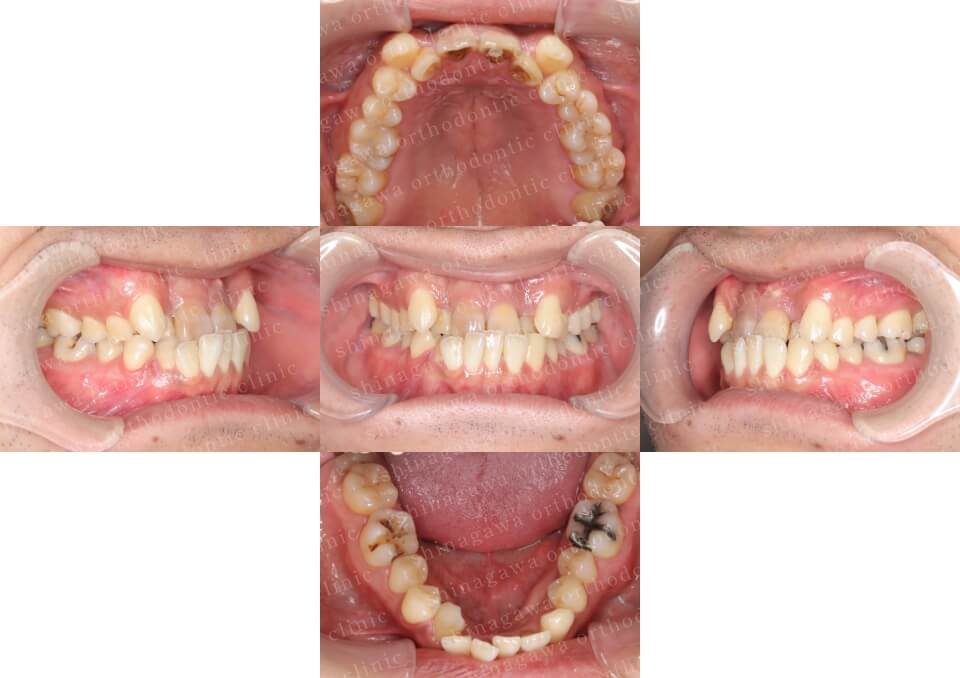

症例2

叢生、正中不一致

| 年齢 | 17 歳 |

|---|---|

| 性別 | 女性 |

| 住所 | 神奈川県横浜市 |

| 主訴 | ガタガタしている, 上下真ん中ずれ |

| 不正咬合の種類(診断) | 叢生, 正中不一致 |

| 装置 | (マウスピース型矯正装置)アライナー |

| 抜歯/非抜歯 | UR4, UL4, LR4, LL4 |

| 期間 | 18M |

| 費用 | 990,000 円 |

| リスク・副作用 | 矯正治療による歯の移動に伴う痛み, 虫歯, 歯肉退縮, 歯根吸収 |